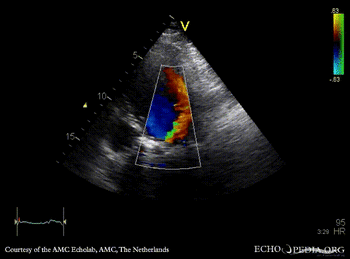

Rocking aortic valve prosthesis

A4CH: rocking aortic valve prosthesis A4CH: Color Doppler, severe aortic regurgitation